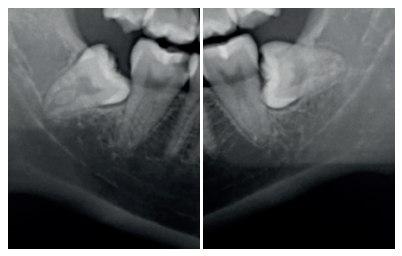

Diagnóstico radiográfico de los caninos maxilares incluidos. Comparación entre dos y tres dimensiones

Introducción: La inclusión de caninos tiene una alta incidencia y plantea varias complicaciones clínicas, siendo de vital importancia el diagnóstico precoz y exacto para minimizar los riesgos y complicaciones derivadas. El objetivo de este trabajo es analizar, utilizando como referencia las líneas planteadas por Alqerban, la efectividad de las dos dimensiones en el diagnóstico volumétrico de la inclusión de los caninos maxilares.

Métodos: Seleccionamos 27 pacientes con 36 caninos maxilares incluidos que se realizaron estudio de ortodoncia con ortopantomografía y tomografía computarizada de haz cónico (Cone Beam Computed Tomography, CBCT) del maxilar en la Clínica Universitaria de la Universidad Europea. Se trazaron tres líneas de referencia basándose en la distancia de la cúspide del canino al plano oclusal (L1), a la línea media (L2) y a su lugar ideal de erupción (L3), tanto en la ortopantomografía como en el CBCT. Como valores de referencia ideales seleccionamos un grupo control de 36 caninos maxilares erupcionados.

Resultados: Se compararon los resultados en dos y tres dimensiones mediante la prueba T de Student, tras comprobar su distribución normal mediante la prueba de contraste de Anderson-Darling. No se obtuvo significación estadística (p>0.05) para ninguna de las variables estudiadas.

Conclusiones: El uso del CBCT es vital para asegurar un buen diagnóstico en cuanto a la posición del canino y su relación con estructuras adyacentes y así establecer un plan de tratamiento adecuado. Aun así, la ortopantomografía aporta información suficiente para la planificación inicial.

Radiographic diagnosis of impacted maxillary canines: Comparison between two and three dimensions

Introduction: An impacted canine is a very common condition and raises several clinical complications. Early and exact diagnosis is important in order to minimise the risks and subsequent complications. The objective of this study is to analyse the effectiveness of two dimensions in the volumetric diagnosis for impacted maxillary canines, using the lines proposed by Alqerban as a reference.

Methods: An orthodontic study of the maxilla using orthopantomography with cone beam computed tomography (CBCT) at the Madrid European University Clinic was performed on 27 patients selected with 36 maxillary impacted canines. Three reference lines were drawn based on the distance from the cusp of the canine to the occlusal plane (L1), to the midline (L2) and to its ideal eruption site (L3), in both the orthopanthomography and the CBCT. As ideal reference values, we selected a control group of 36 erupted maxillary canines.

Results: The results were compared in 2 and 3 dimensions using the Student’s t test, after verifying their normal distribution using the Anderson-Darling contrast test. Statistical significance (p > 0.05) was not obtained for any of the variables studied.

Conclusions: The use of CBCT is vital to ensure good diagnosis of the canine position and its relationship with adjacent structures and thus establish an adequate treatment plan. However, orthopantomography provides sufficient information for initial planning.